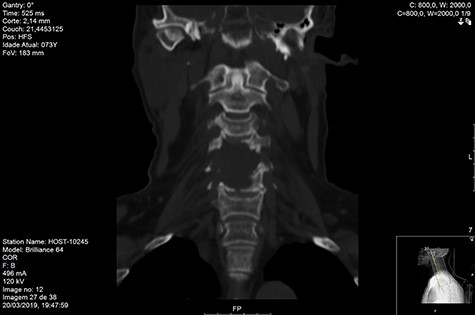

MRI and CT scans performed at 90 days post-radiation therapy showed an arrest of further progression of instability and resolution of the lytic lesion (Figs 7–13).

Computed tomography (CT) (Figs 1–3) and magnetic resonance imaging (MRI) (Figs 4–6) of the cervical spine were performed and revealed a lytic lesion involving most of C4, C5 and C6 vertebral bodies with bilateral extension to the posterior spinal elements of C4 and C5 and complete disruption of C4-C5 and C5-C6 intervertebral discs.

The Spinal Instability Neoplastic Score (SINS) [4, 6, 7] for assessing spinal instability from metastatic disease was used and the lesion was deemed unstable (SINS 13), with impending risk of increased neurological damage.